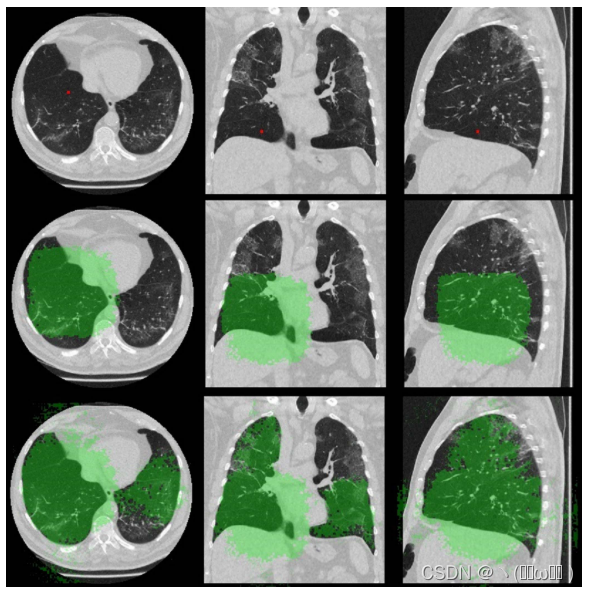

我们将叶分割问题定义为体素分类问题。 给定扫描 I,目标是预测每个空间位置 i 的体素标签 l^i,其中 l^i ∈ 标签集 L ={0, 1, 2, 3, 4, 5} 表示背景,左上,左下 、右上叶、右下叶和右中叶。 在本文中,我们使用具有两个级联 CNN 的多分辨率方法来捕获叶分割的全局上下文和局部细节,如 [15] 中所提出的。 我们的框架如图 1 所示。除了使用多分辨率框架外,我们还引入了一种新颖的非本地模块来捕获结构化关系,并且我们高效的网络设计允许对我们的多分辨率框架进行端到端训练。 对于每个 CNN,我们放置我们提出的非局部模块以最粗略的分辨率聚合特征的关系信息,因为这些特征通常表示高级语义,例如对象和对象部分 [34]。 所提出的非局部模块计算这些特征之间的视觉和几何对应关系,自然地建模对象和对象部分之间的关系。 几何信息的使用受到 [14] 的启发。 此外,所提出的非局部模块可以扩大这些特征的感受野,因为一个非局部响应的计算涉及特征图中的所有特征。 我们将在每个阶段都带有提议的非本地模块的 CNN 称为关系 U-Net (RU-Net),详细信息将在本节后面进行解释。

图1:具有两个 CNN 级联的叶分割框架的概述。 在每个阶段,CNN(RU-Net)使用提出的非局部模块来捕获对象和对象部分之间的结构化关系。 RU-Net I 的输出与裁剪的 3D 补丁连接,作为 RU-Net II 的输入。

从理论上讲,所提出的非本地模块可以有效地实现全局接受场,而不是使用积极的下采样输入或依赖更深层次的CNN架构。为了测量非局部操作之前和之后的有效感受野 (ERF) 大小,我们计算了特征映射F中位置I处的特征到输入图像i的梯度,即我们在新型冠状病毒肺炎测试装置的ct扫描中对第一个RU网进行正向传递。在图3中,对于三个正交切片,在非本地操作之前和之后在相同对应位置处的特征的ERF可视化。

该图以绿色呈现非零梯度,并以红色正方形指示ERF的中心。中心是通过上采样从特征图中选择的特征到输入图像的映射坐标。因此,可能会发生轻微的偏移。左图显示了由于堆叠卷积的性质而将非局部操作包含在正方形中之前的ERF。但是,右侧非局部后的ERF显示为非正方形分布,到达肺的另一侧。因此,我们得出结论,非局部模块可以显着扩大有效感受野。

为了研究特征之间的结构化关系,我们在给定特征图x和几何特征 μ 的情况下,可视化了位置i处特征的自我注意权重。我们对新型冠状病毒肺炎测试装置的两次ct扫描进行了第一阶段RU-Net的正向传递。注意权重是来自等式2的与f(xi,x j ) τ(μ i,μ j) 相对应的自注意矩阵中的第i行向量。图4 (a) 显示了位置i的特征 (绿点) 主要取决于健康肺存在时肺叶内的信息。我们还可以清楚地看到注意力权重跟随肺叶边界。图4 (b) 显示了多个毛玻璃病变的病例,其中代表右中叶附近区域的特征与在整个肺中呈现其他区域的特征之间的相互作用。有趣的是,我们注意到,通过在非局部模块中引入几何术语,注意力权重也对应于肺边界框。

图3:通过在 COVID-19 测试集的 CT 扫描上对第一个 RU-Net 运行前向传递,在非本地模块(第 2 行)之前和之后(第 3 行)之前的有效感受野 (ERF)。绿色区域表示输入扫描中对应于红色方块(第 1 行)的位置处的特征的非零梯度(相对于输入扫描)。

图4:来自提议的非局部模块的Self-Attention权重(第2行),用于使用原始输入扫描(第1行)中的绿点显示其位置的特征。 我们为此图使用彩色地图喷射 [39]。 显示了来自 COVID-19 测试集的两次扫描。 (a) 主要展示了清晰肺叶内的特征依赖性。 (b) 表示当目标叶受到疾病影响时需要长期依赖。